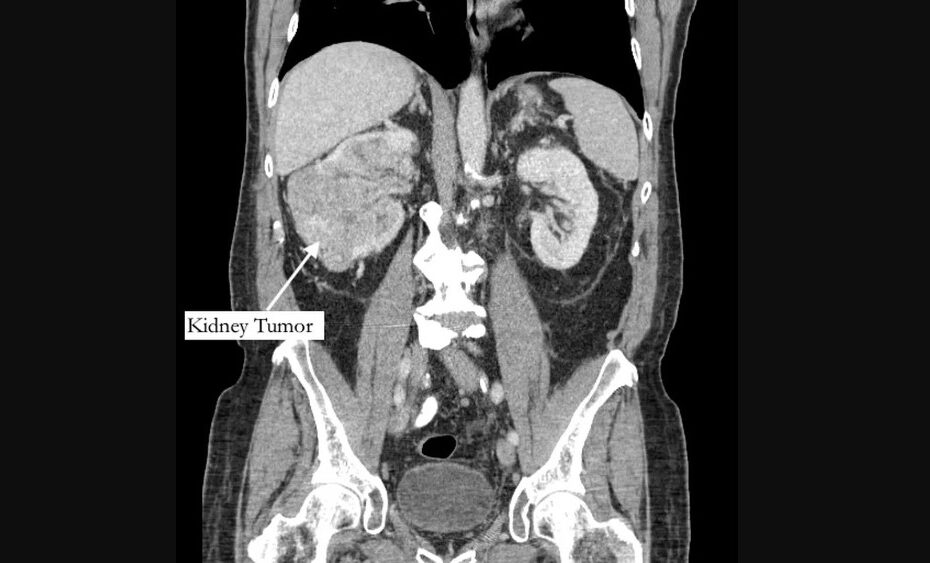

O que era apenas uma consulta por uma dor no dedão do pé direito terminou sendo o diagnóstico de um tumor em fase terminal para um aposentado dos Estados Unidos.

Segundo o jornal “New York Post”, Richard Bernstein, 42, sentia a dor havia cinco anos, e pensava que se tratava de uma fratura, mas recebeu o diagnóstico de grande tumor no rim e de um trombo tumoral, um tumor que se estende até um vaso sanguíneo.

Depois dois anos de visitas a podólogos e fisioterapeutas, que nunca achavam nenhum problema nos ossos, ele recorreu a um especialista de medicina esportiva, que suspeitou de estenose espinhal, que pode pressionar a nervos da coluna vertebral.

No entanto, os sintomas começaram a aumentar. A dor subiu para o tornozelo e, em março deste ano, sua perna começou a inchar. Foi só aí que um médico pediu um exame abdominal, que revelou o tumor.